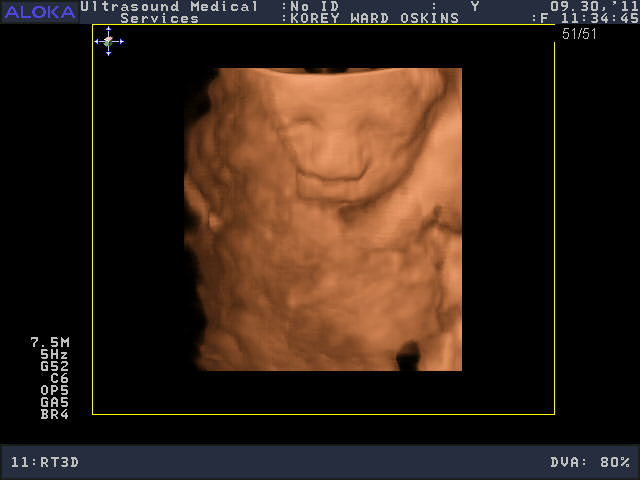

He was a very stubborn baby, so it was really kind of nerve-wracking at first thinking we might not get a single good picture. His face was squished up against the placenta and he wouldn’t budge. You’ll see that in the pictures below; it looks like an enveloping cloud or a scallop shell. Finally he moved a bit and we got some glimpses of his face. We saw him make some facial expressions, wiggle his fingers, and move his mouth around. We were curious to see whose nose he would have, and in some pictures, it looks like he has Josh’s, in others, mine.

So who do you think he looks like?

He is sooooo cute! Personally, I think he looks like ME.